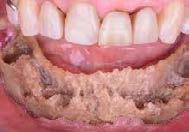

Imagen 8. Osteorradionecrosis de los maxilares Imagen 7. Osteorradionecrosis de los maxilares.

La situación cambia radicalmente en las etapas de irradiación y postradiación. Como ya se ha mencionado, el tejido óseo irradiado es “3 H”, hipocelular, hipovascular e hipóxico, por lo que al no tener capacidad de regeneración, las exodoncias y cualquier otro procedimiento que implique trauma a estos tejidos, deben evitarse hasta por un periodo de 10 años posteriores a la radioterapia (Imagen 7 y 8).

Uno de los preceptos establecidos y aceptados universalmente para garantizar la asepsia y el éxito de la terapia endodóntica es el aislamiento absoluto del campo operatorio. Sin embargo, esto no aplica en este tipo de pacientes, pues resulta técnicamente imposible colocar la grapa por 2 razones: 1) La escasa o nula estructura coronaria dental remanente y 2) La grapa puede provocar lesión en tejidos blandos, periodonto y hueso alveolar. Por lo que el tratamiento se realizará con aislamiento relativo (Imagen 9).